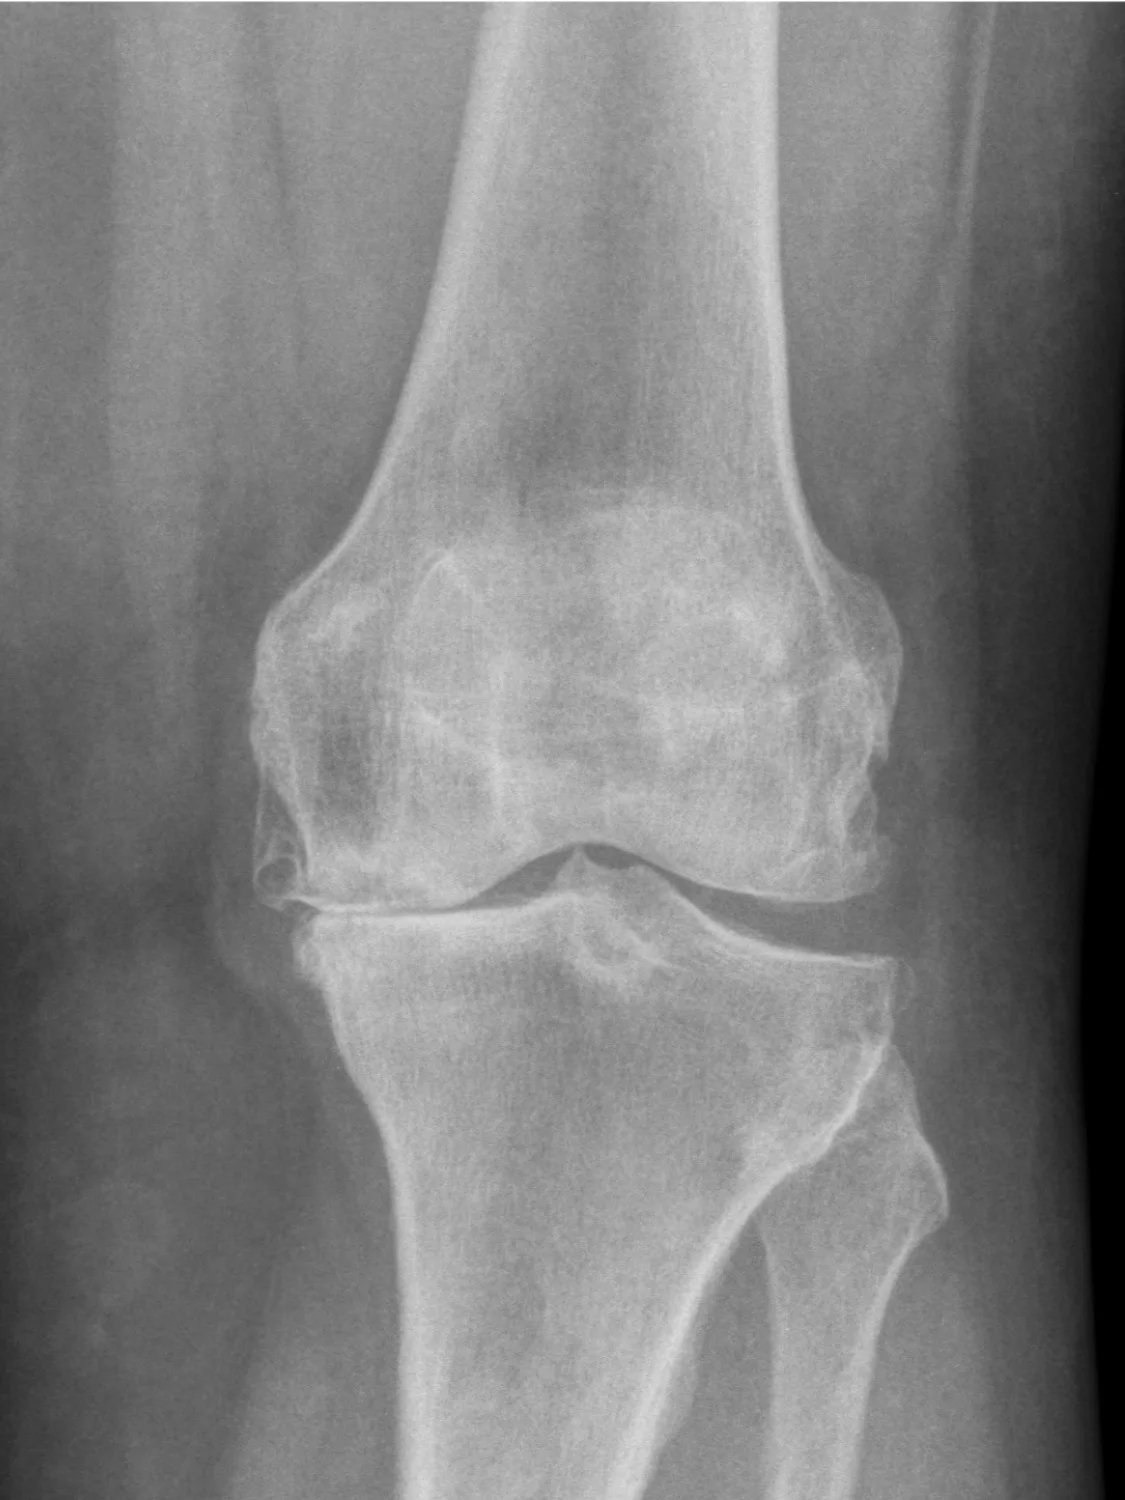

Artrose de Joelho